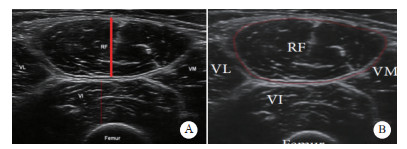

1.2.2.3 超声测量参数及方法(1)测量参数:收集患者入组后1、3、5、7 d股直肌厚度及横截面积。测量方法由2名具有5年的超声检查经验的超声科医师带领一名接受床旁超声培训的ICU医师进行股直肌测量,主要测量参数为股直肌厚度(Thickness of rectus femoris muscle, RF-MLT)与股直肌横截面积(rectus femoris cross sectional area, RF-CSA)[12]:受试者接受超声检查时均取平卧位,床头抬高0°,下肢放松,双膝伸直且放松,脚趾伸直指向天花板,在髂前上棘和髌骨上缘连线的中点测量股直肌厚度,确保探头给予最小压力,探头长轴与大腿长轴保持垂直,横向扫描,扫描深度设置为可以识别股骨方向的位置,获得最佳股骨回声以保证探头垂直于目标肌肉,采集图像,股直肌厚度则取呈高回声的筋膜间的内部垂直距离,重复测量3次,直到3次测量差别在10%以内,并计算这3次测量值的平均值;在髂前上棘和髌骨上缘连线的中下三分之一处测量股直肌横截面积,方法同上,利用超声软件勾画筋膜内回声线并自动计算面积,重复测量3次,直到3次测量差别在10%以内,并计算这三次测量值的平均值,见图 1。

| 注:图A为超声显影的股直肌厚度及测量区域,图B为超声显影的股直肌横截面积及测量区域 图 1 超声测量区域示意图 Fig 1 Schematic diagram of the ultrasound measurement area |